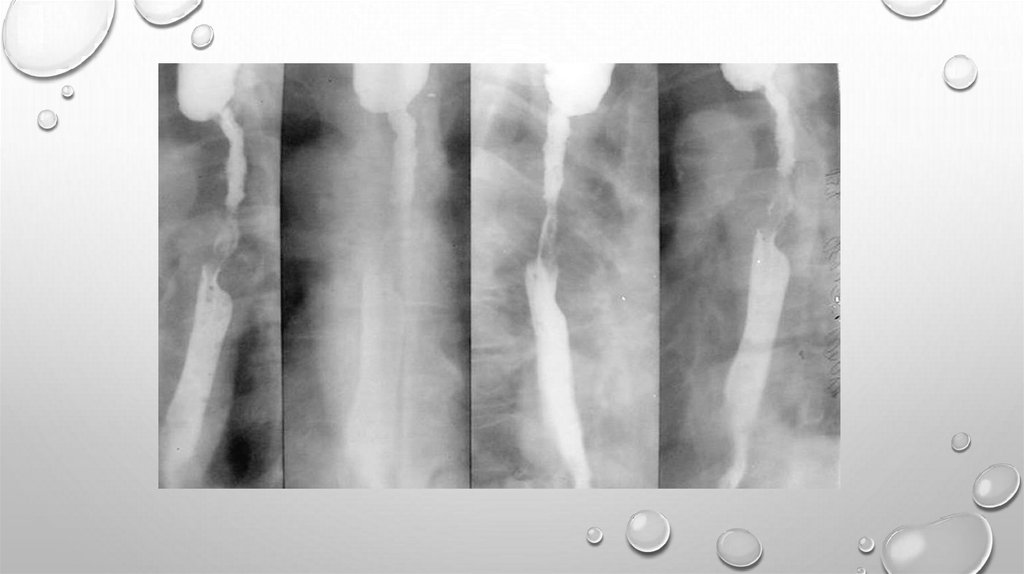

ДИАГНОСТИКА

РЕНТГЕНОЛОГИЧЕСКОЕ ИССЛЕДОВАНИЕ С

КОНТРАСТИРОВАНИЕМ ПИЩЕВОДА ВЗВЕСЬЮ БАРИЯ

ВЫЯВЛЯЕТ ОПУХОЛЬ, ЕЕ ЛОКАЛИЗАЦИЮ, ДЛИНУ

ПОРАЖЕНИЯ И СТЕПЕНЬ СУЖЕНИЯ ПИЩЕВОДА,

ИЗМЕНЕНИЯ В ЛЕГ КИХ И ПЛЕВРАЛЬНЫХ ПОЛОСТЯХ.

ХАРАКТЕРНЫЕ СИМПТОМЫ РАКА — ДЕФЕКТ

НАПОЛНЕНИЯ, "ИЗЪЕДЕННЫЕ" КОНТУРЫ ЕГО,

СУЖЕНИЕ ПРОСВЕТА, РИГИДНОСТЬ СТЕНОК

ПИЩЕВОДА, ОБРЫВ СКЛАДОК СЛИЗИСТОЙ ОБОЛОЧКИ

ВБЛИЗИ ОПУХОЛИ, ПРЕСТЕНОТИЧЕСКОЕ

РАСШИРЕНИЕ ПИЩЕВОДА.